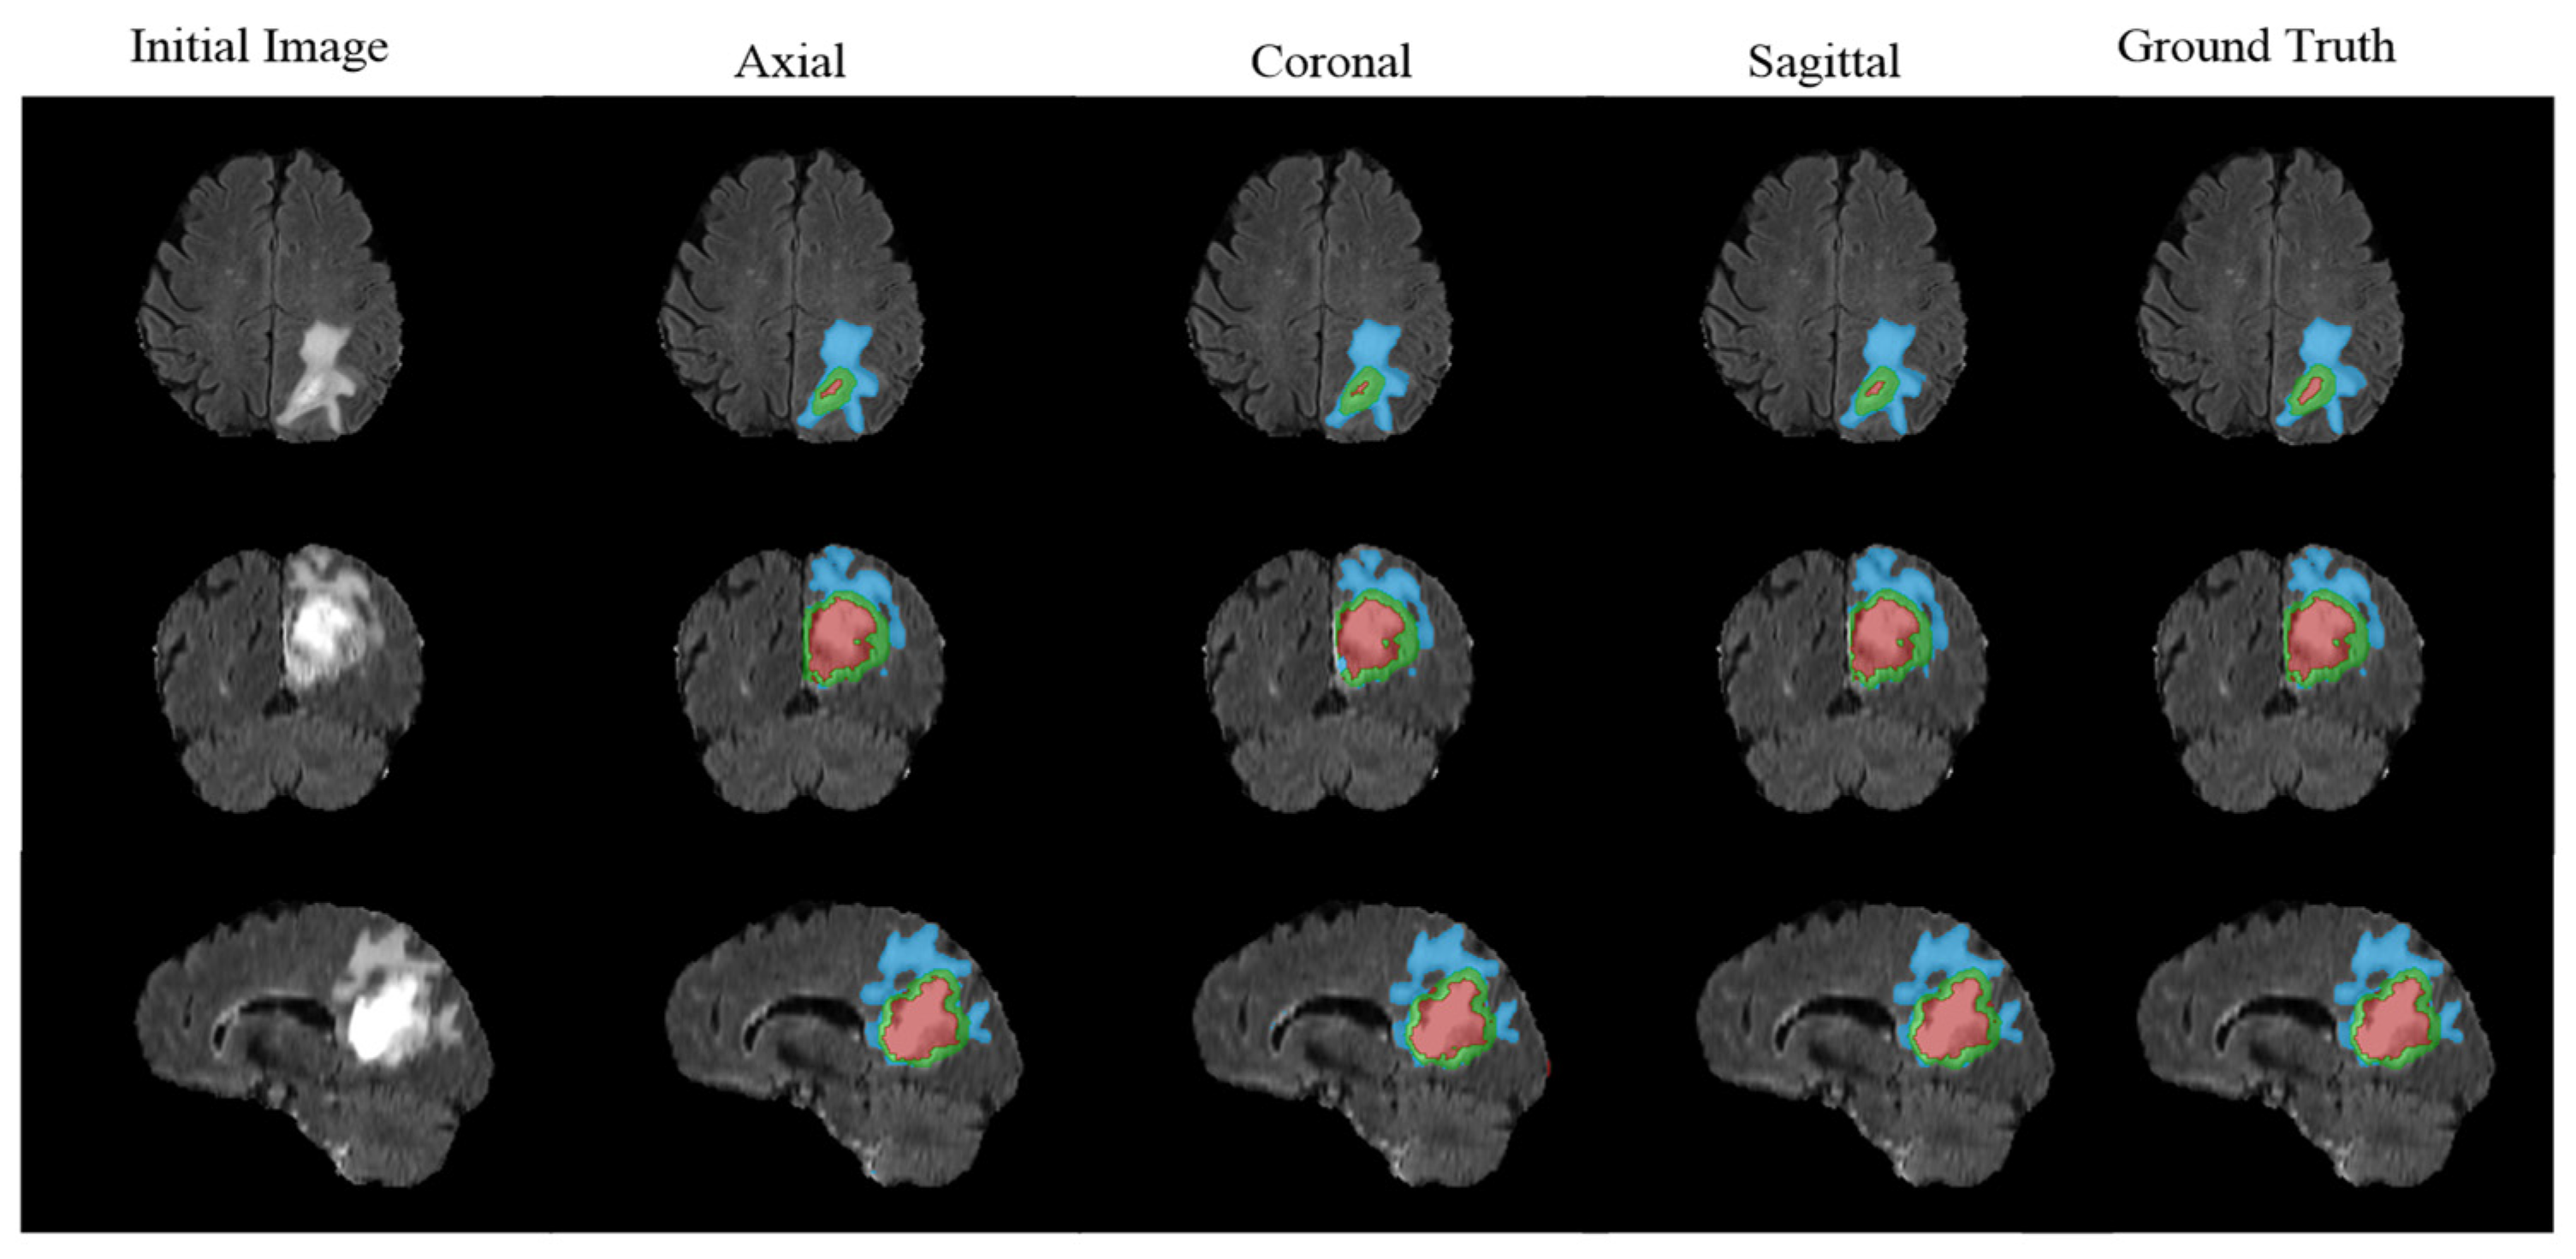

3.5. The Effectiveness of DDPM in Segmentation Tasks

Researchers applied DDPM to denoise and segment magnetic resonance imaging (MRI) images, enhancing the visibility of tissue boundaries. The model’s probabilistic framework provided uncertainty estimates, aiding in distinguishing tissue regions from MRI images. As shown in Figure 2, segmenting tissue in MRI scans is a critical task for treatment planning and monitoring disease progression [13,42].

Figure 2.

Schematic diagram of brain MRI glioma segmentation.